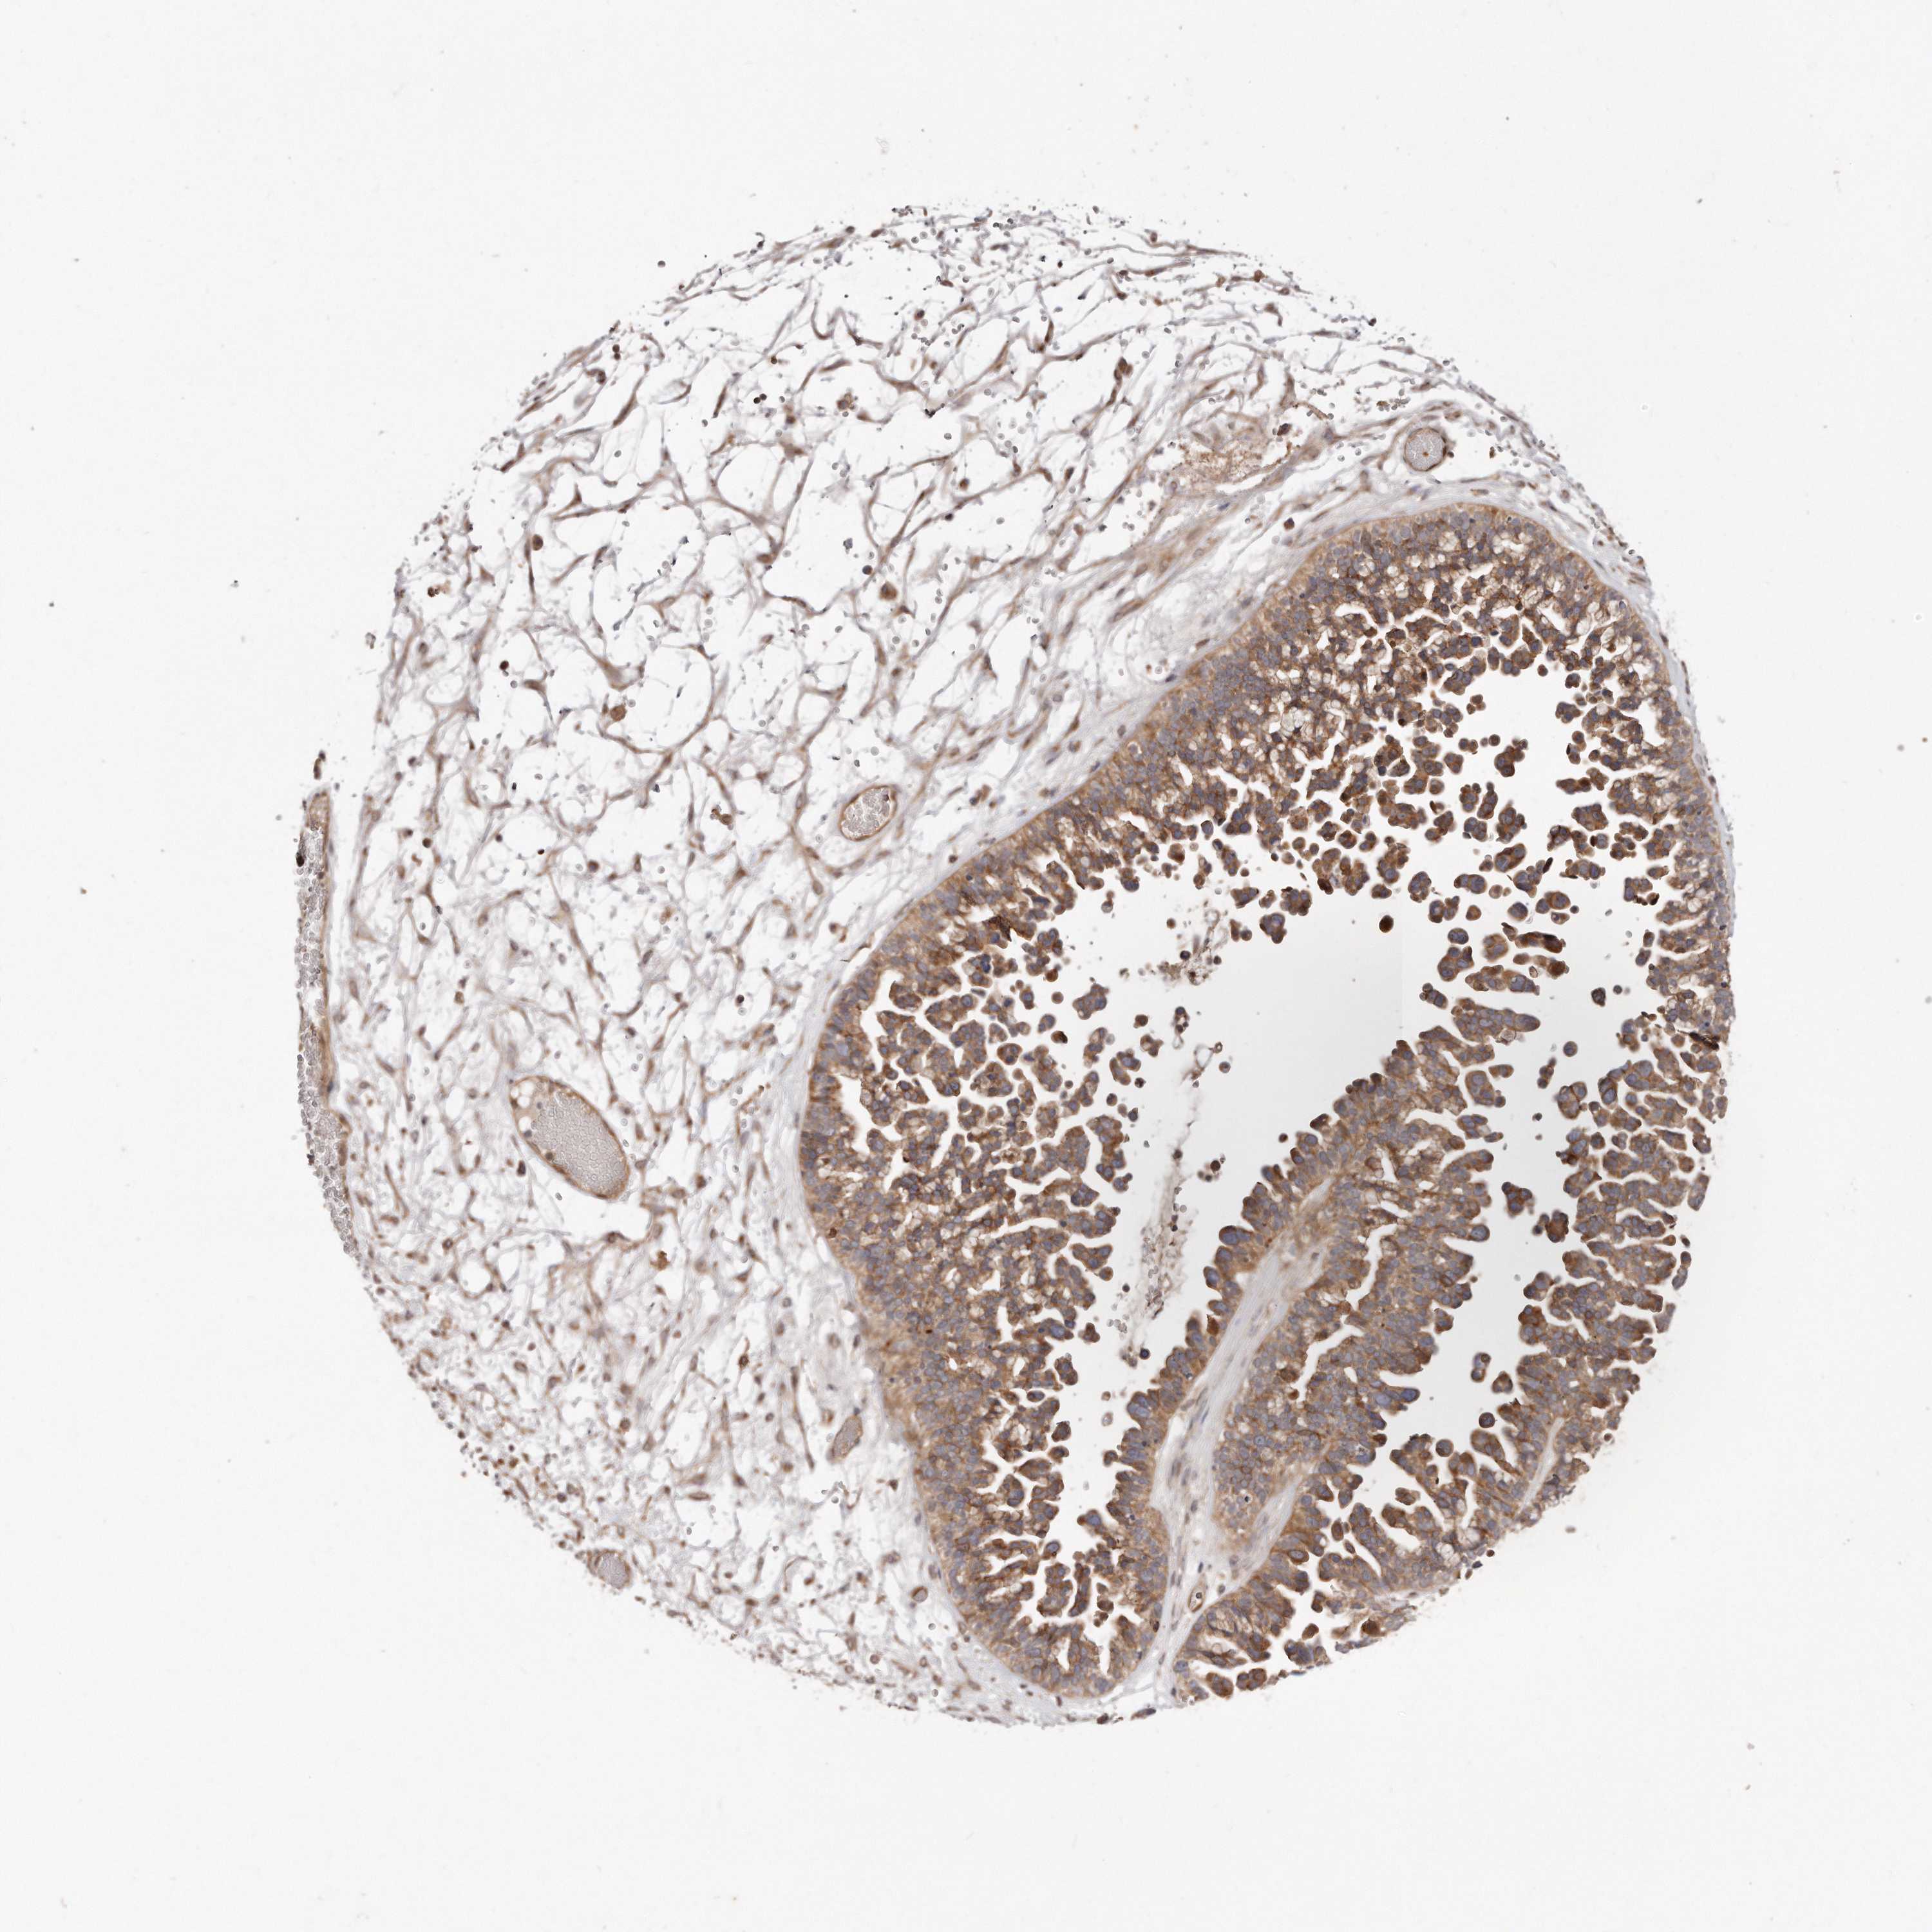

OVARIAN CANCER - Protein expressioni

A mouse-over function shows sample information and annotation data. Click on an image to view it in a full screen mode. Samples can be filtered based on level of antibody staining by selecting one or several of the following categories: high, medium, low and not detected. The assay and annotation is described here.

Note that samples used for immunohistochemistry by the Human Protein Atlas do not correspond to samples in the TCGA dataset.

Antibody stainingi

Antibody staining in the annotated cell types in the current human tissue is reported as not detected, low, medium, or high, based on conventional immunohistochemistry profiling in selected tissues. This score is based on the combination of the staining intensity and fraction of stained cells.

Each image is clickable and will lead to virtual microscopy that enables deeper exploration of all samples and also displays staining intensity scores, fraction scores and subcellular localization as well as patient and tissue information for each sample.

Antibody HPA030101

Staining

High

Medium

Low

Not detected

Intensity

Strong

Moderate

Weak

Negative

Quantity

>75%

75%-25%

<25%

None

Location

Nuclear

Cytoplasmic/membranous

Cytoplasmic/membranous,nuclear

Cystadenocarcinoma, serous, NOS

Carcinoma, endometroid

Cystadenocarcinoma, mucinous, NOS

Carcinoma, NOS